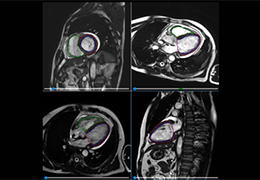

分析智能。

这些功能利用数字控制面板分析运营、业务和临床绩效。

使管理员能够跟踪关键参数,包括平均曝光率、拒绝的影像和探测器统计信息。

帮助确定需要改进的方面,支持为员工和部门制定适当的改进计划。